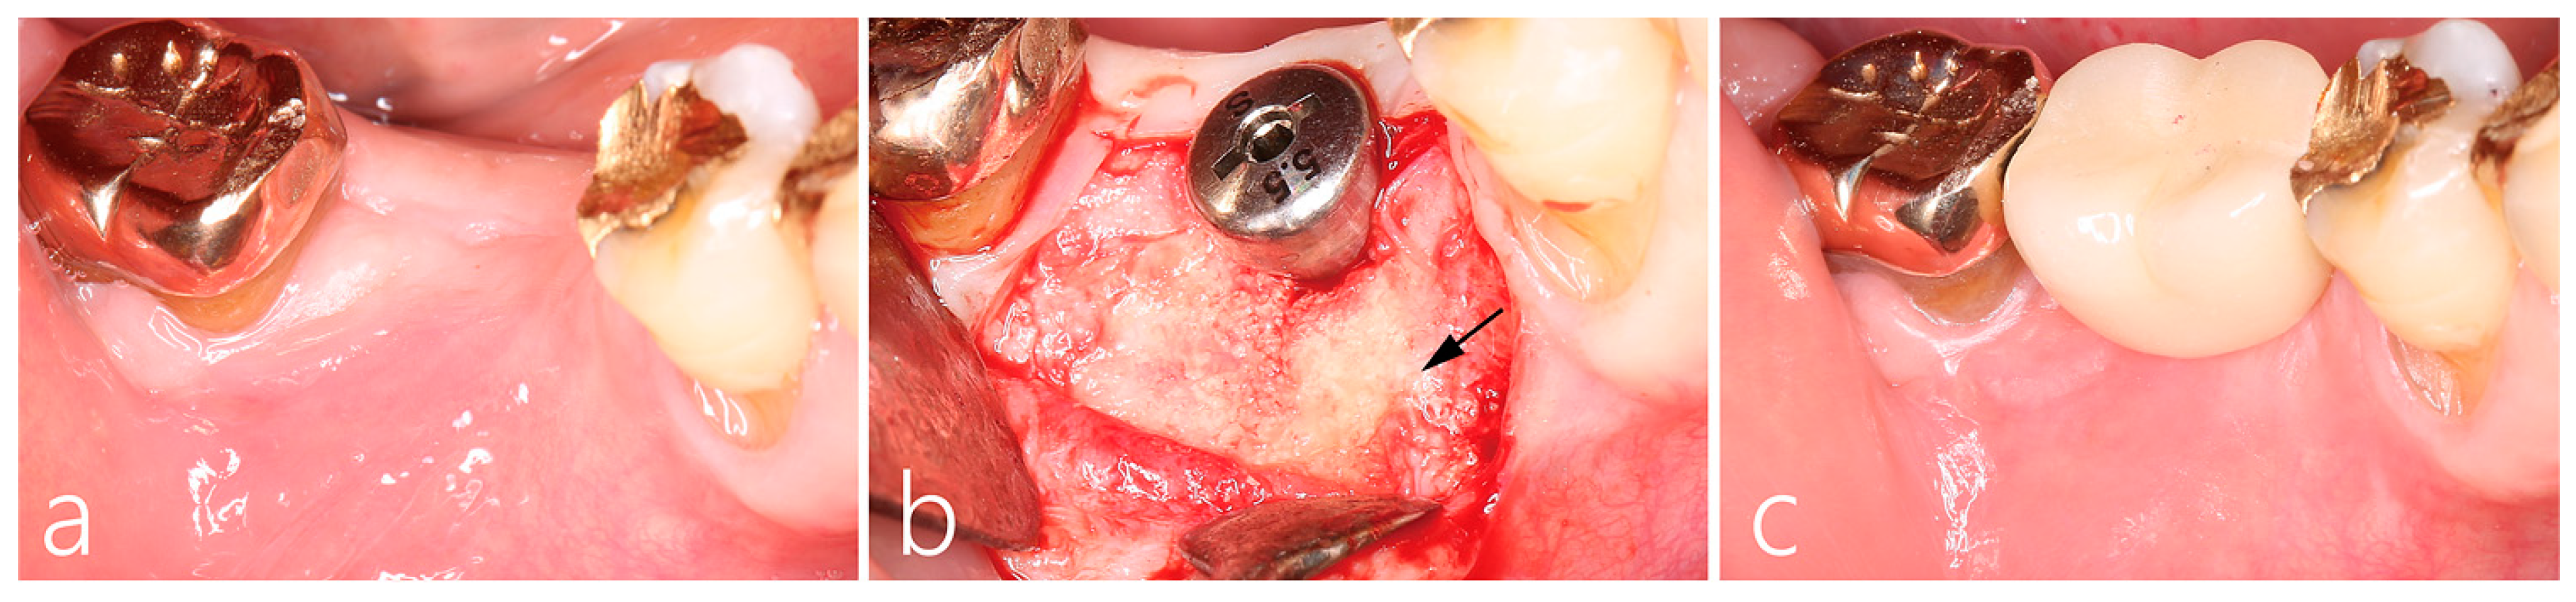

2.2. Uncovering Procedure

2.3. Prosthesis Delivery and Follow-Up